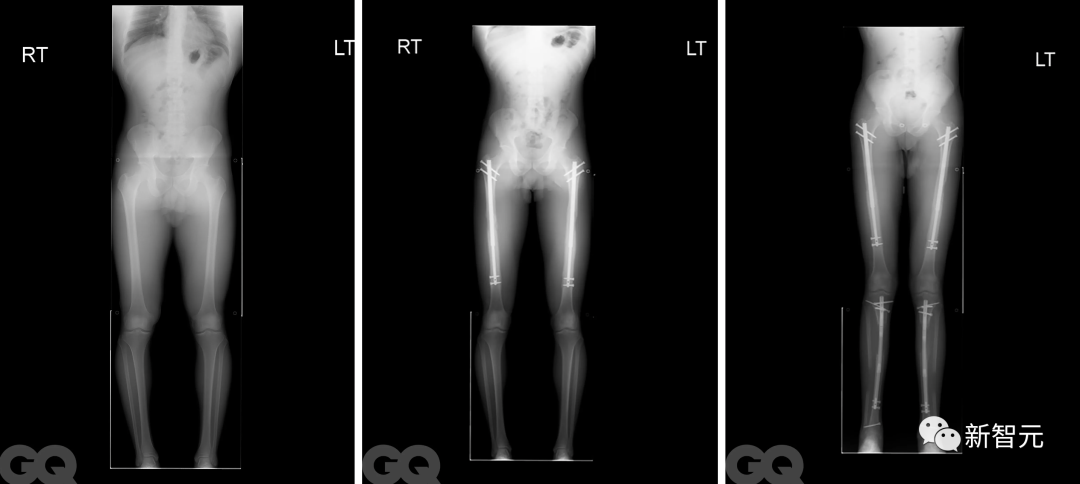

为了完成手术,医生需要将患者的股骨或大腿骨折断,然后将可调节的钛制金属钉插入其中,大约有短笛那么长。

如图所示:

未来三个月,这些钉子每天都会通过一个磁性遥控器延长1mm,逐渐让腿部愈合。

一位患者术前术后X光片,肉眼可见其股骨和胫骨都被拉长,身高增加了6英寸

John Lovedale进行腿部延长手术前后对比(左)